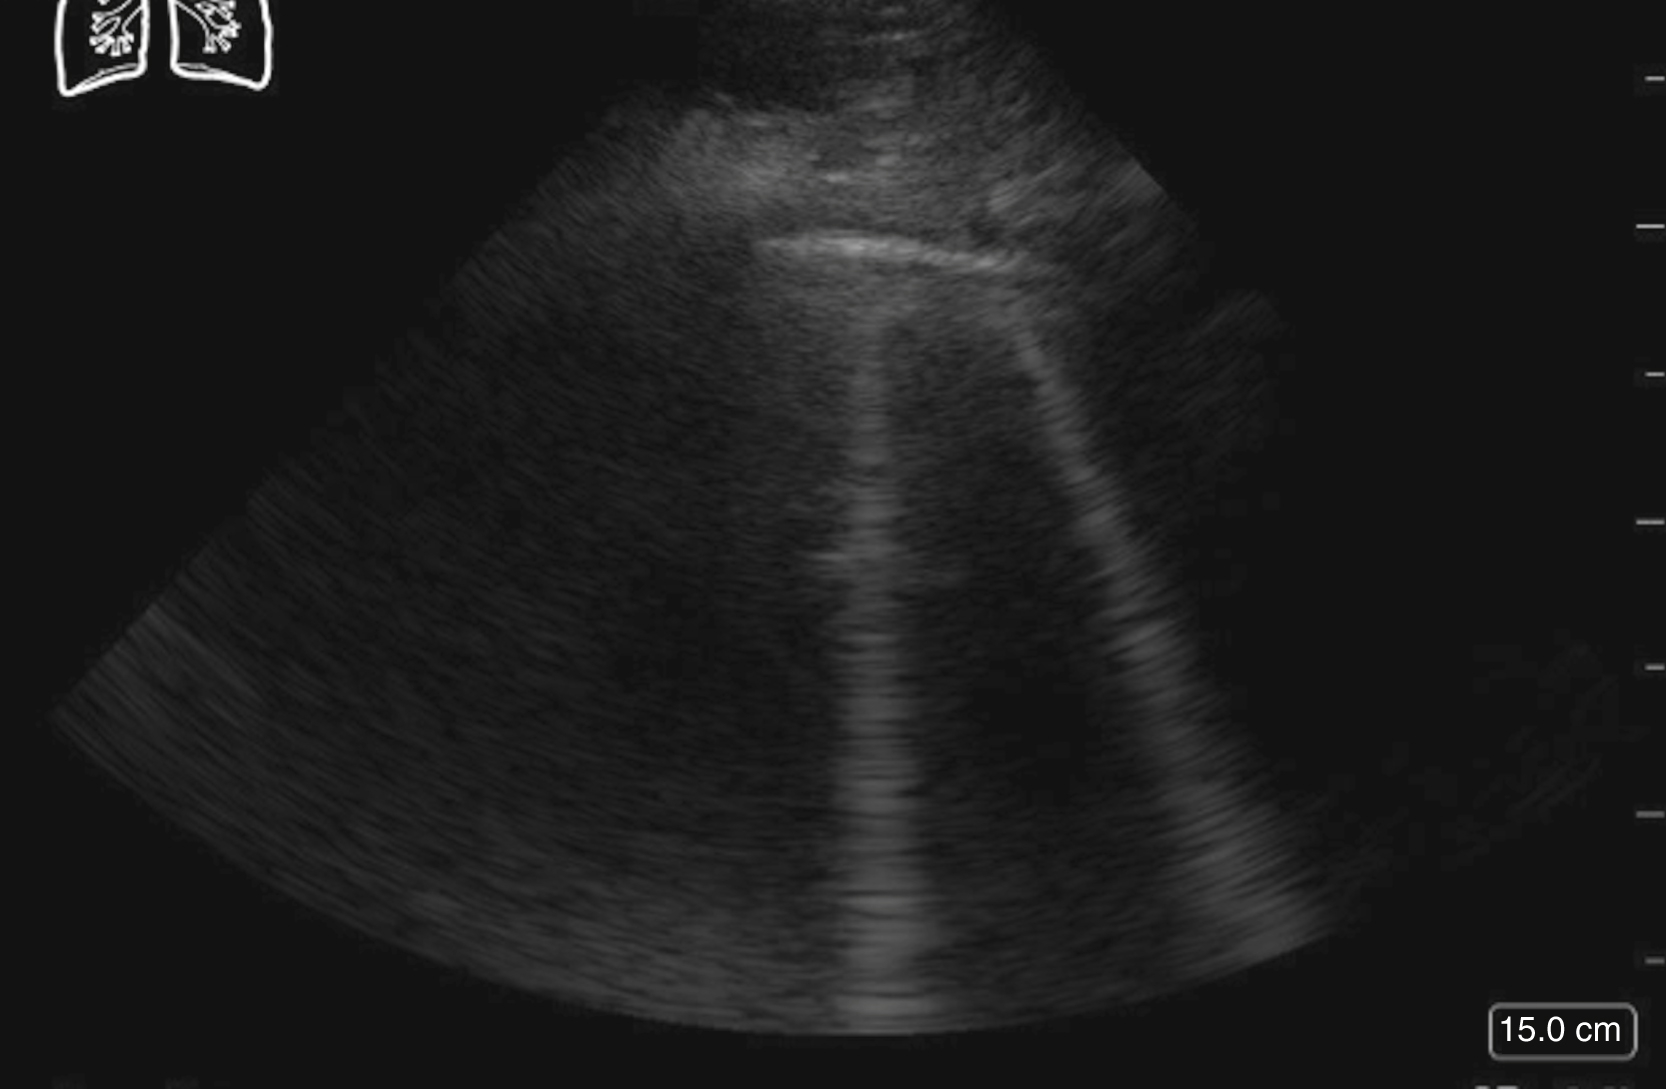

Thoracic US is often performed with a low-frequency curvilinear array or phased array transducer, although visualization of lung sliding may be enhanced, if necessary, by the use of a high-frequency linear array transducer. The original BLUE (Bedside Lung Ultrasound in Emergency) protocol evaluated 4 areas on each hemithorax, but subsequent studies have looked at a number of protocols and additional areas of the anterior, lateral, and posterior thorax. Lung sliding, a normal finding, is identified as the visceral and parietal pleura gliding against each other during normal respiration. A lines, horizontal equally spaced echogenic artifacts deep to the pleural line, are also a normal finding ( Fig. e3.14 ).

A lines signifying normal lung.